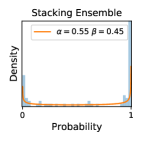

5.1 Distribution of Uncertainty Scores

In contrast, the MC-dropout method showed the worst overall performance among the three, as it can be seen from the high ratios of SL0 examples among the uncertain negatives in Figure 4. The histograms in Figure 2 provides another perspective to look into the phenomenon, where a decent proportion of MC-dropout model’s predictions on SL0 inputs entailed low confidence (far from 0 or 1), which from another angle explained why MC-dropout was less specific in terms of lower FNP; many no-DR inputs (i.e. SL0) were erroneously assigned high uncertainty by MC-dropout models.

It is still an open question why the evaluated MC-dropout networks signaled relatively high uncertainty on SL0 & SL3 & SL4 data that are less likely to be ambiguous. We conjecture that much of the “uncertainty” indicated by disagreement among test-time dropout samples actually reflects the stochastic nature of dropout networks rather than the real decision uncertainty associated with the data. It is worth noting that the MC-dropout model we evaluated was not weak per se; they all achieved above Area Under Curve (AUC) scores on test sets. The weakness of individual test-time samples (which explains their low-confidence predictions on SL0 & SL3 & SL4) might have been hidden when they are aggregated into an ensemble—a well-known advantage of ensemble learning. Our results suggested that the uncertainty information given by implicit ensemble methods such as MC-dropout and TTA might not be as reliable as that from explicit ensemble approaches (e.g., stacking ensembles). Similar findings on MC-dropout can be found in some previous papers [1].